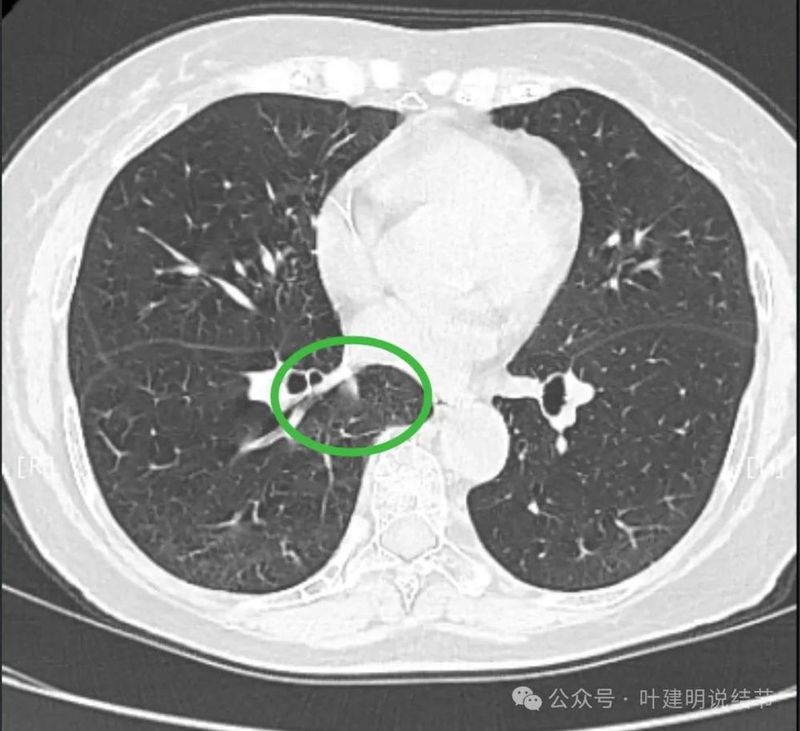

天蓝色箭头示病灶与支气管之间有缝隙,但贴的较近;黄色箭头示支气管管腔;红色箭头示病灶,边缘光滑。

支气管受压,但无明显破坏;与支气管之间紧贴位有的位置仍有缝隙;病灶边缘光滑。

病灶密度较为均匀,对支气管是压迫后移位。表面光滑。

似乎有血管穿过。

边缘光滑,没有毛刺,膨胀性生长。

表面光滑,内部密度较均匀,边界清楚,膨胀性长。

没有侵犯邻近支气管。

边缘光滑,分叶不明显。

上图这个层面感觉病灶与肺血管之间没有明显间隙,似像侵犯或愈着的样子。

结节边缘区域与血管之间又有间隙了的。

下肺静脉水平,病灶基本没有了。